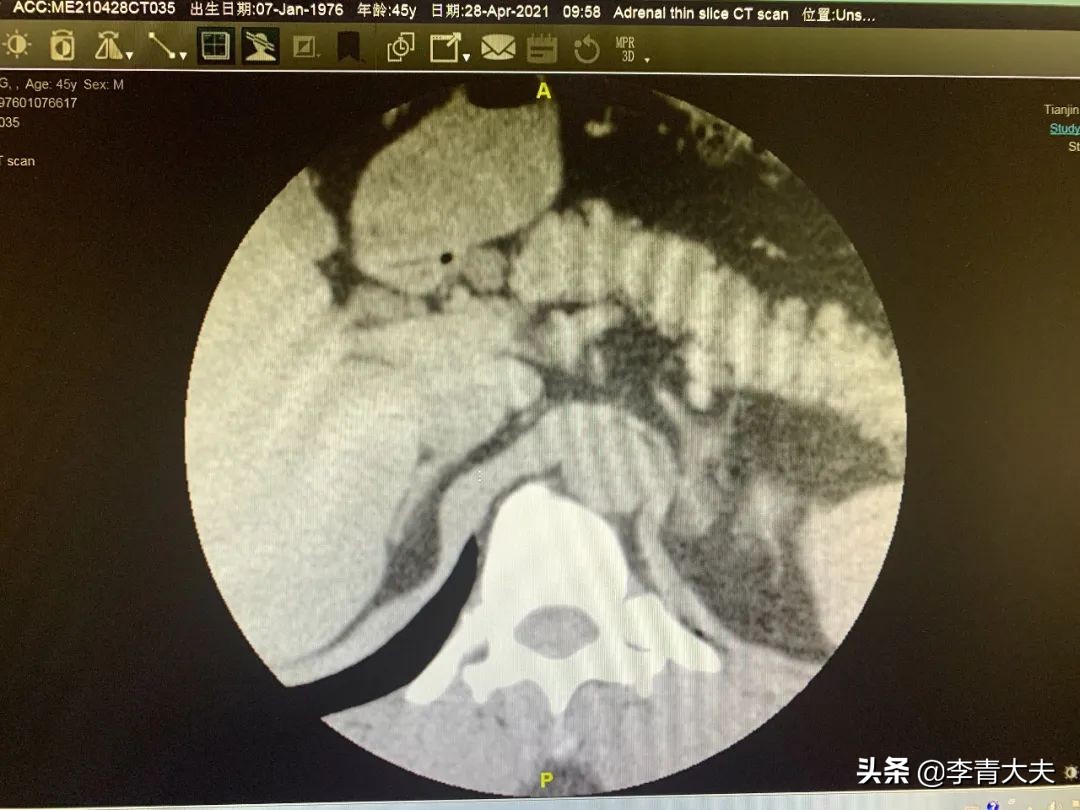

高血压、低血钾,而且30多岁发病,几种降压药都降不到正常,我高度怀疑是原发性醛固酮增多症(原醛),于是给他查了肾上腺薄层CT和高血压三项。果不其然,血醛固酮增高,左肾上腺腺瘤伴有增生。